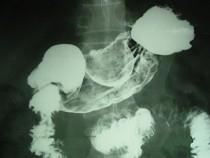

问题 男,52岁,中上腹痛,影像检查如图,最可能的诊断是 ( )

选项 A.慢性肥厚性胃炎 B.胃癌 C.胃溃疡 D.胃平滑肌瘤 E.胃平滑肌肉瘤

答案 D